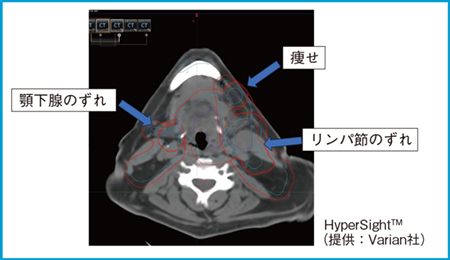

HyperSightを用いたARTの実践

今回,当院ではHyperSightを用いて,頭頸部癌に対しoffline-ARTのワークフローでARTを実践した。実際に初回CTのCTVやGTV,PTVをCBCTの画像に重ねると,顎下腺やリンパ節のずれ,痩せが認められた(図1)。また,CBCTの画質が驚くほど向上し,より客観的な判断が可能になったと感じた。ビームおよびMUを変えずに,CBCT上で線量計算してみると,喉頭線量がmean dose 67 Gyを超えており,PTVの最大線量が処方線量の113%と非常に高くなっていた。これでは実施不可で,リプランを実施するという判断をすることになった。このような判断をカウチ上で行えることになる。

図1 HyperSightによるoffline-ARTワークフローの改善